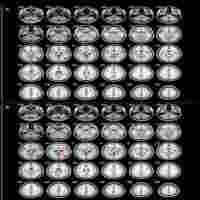

Comparison of regional cerebral blood flow and glucose metabolism in the normal brain: effect of aging

| Abstract | The regional cerebral blood flow (rCBF) and metabolic rate for glucose (rCMRGlc) are associated with functional activity of the neural cells. The present work reports a comparison study between rCBF and rCMRGlc in a normal population as a function of age. 10 young (25.9+/-5.6 years) and 10 old (65.4+/-6.1 years) volunteers were similarly studied at rest. In each subject, rCBF and rCMRGlc were measured in sequence, during the same session. Both rCBF and rCMRGlc values were found to decrease from young (mean rCBF=43.7 ml/100 g per min; mean rCMRGlc=40.6 micromol/100 g per min) to old age (mean rCBF=37.3 ml/100 g per min; mean rCMRGlc=35.2 micromol/100 g per min), resulting in a drop over 40 years of 14.8% (0.37%/year) and 13.3% (0.34%/year), respectively. On a regional basis, the frontal and the visual cortices were observed to have, respectively, the highest and the lowest reduction in rCBF, while, for rCMRGlc, these extremes were observed in striatum and cerebellum. Despite these differences, the ratio of rCBF to rCMRGlc was found to have a similar behavior in all brain regions for young and old subjects as shown by a correlation coefficient of 88%. This comparative study indicates a decline in rCBF and rCMRGlc values and a coupling between CBF and CMRGlc as a function of age. |